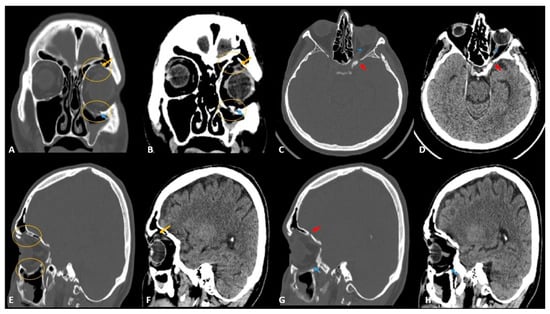

- Betts, A.M.; O’brien, W.T.; Davies, B.W.; Youssef, O.H. A systematic approach to CT evaluation of orbital trauma. Emerg. Radiol. 2014, 21, 511–531. [Google Scholar] [CrossRef] [PubMed]

- Lee, H.-J.; Jilani, M.; Frohman, L.; Baker, S. CT of orbital trauma. Emerg. Radiol. 2004, 10, 168–1672. [Google Scholar] [CrossRef] [PubMed]